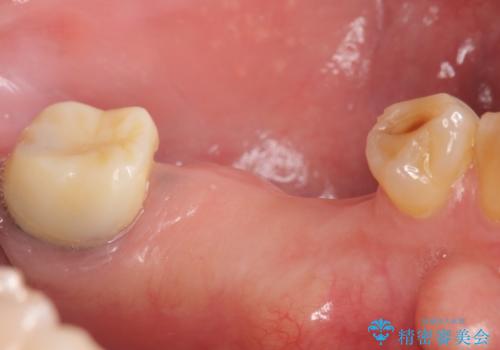

欠損部位である左下5、6番目にインプラントを埋入し、オールセラミッククラウンによる補綴を行いました。

左下7番目は再根管治療を行い、オールセラミッククラウンによる補綴を行いました。

カスタムアバットメントは患者様それぞれの歯茎に合わせて製作されたオーダーメイドのアバットメントです。

既製のアバットメントに比べ適合がよく、高い清掃性を誇ります。

今回用いたオールセラミッククラウンはジルコニアフレームという白い素材の上にセラミックを盛っているため、審美性が非常に高いのが特徴です。

また、ジルコニアは人工ダイヤモンドの材料にも使われているほど高い強度を持っており、そのためオールセラミッククラウンは審美性だけでなく、奥歯やブリッジの補綴も可能とするクラウンです。